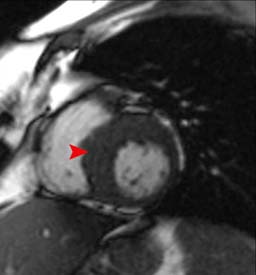

This three chamber view in a patient with HOCM shows a hypertrophied LV and abnormal systolic anterior motion (SAM) of the anterior mitral valve leaflet. It is this SAM that results in obstruction in the LVOT as demonstrated by turbulent flow (flow void).